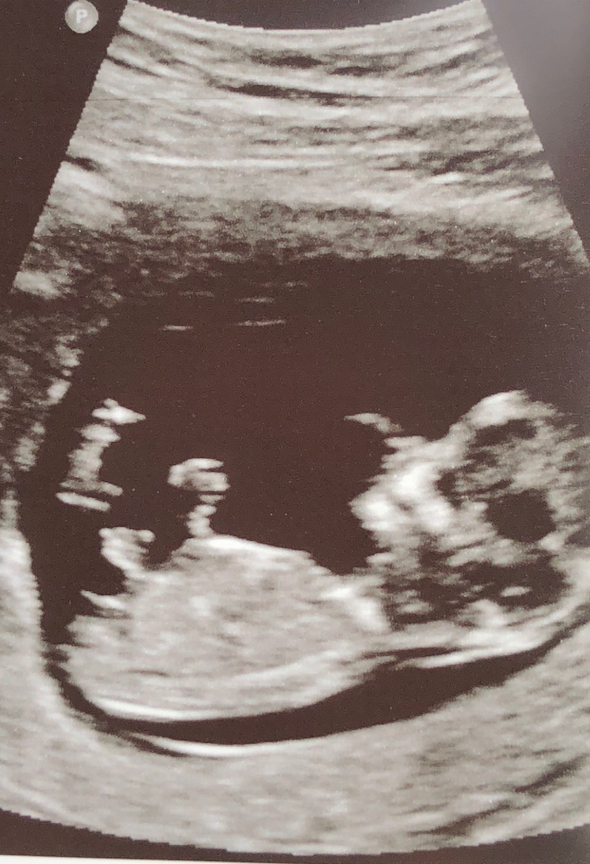

Guessing boy

What is exact gestation? If early in 12th week slight boy lean